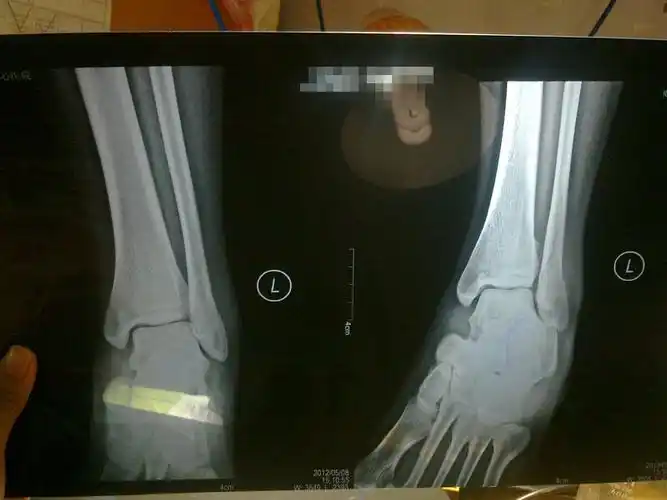

左外踝骨折

第二天去看的时候,医生说是左外踝撕脱性骨折,现在已经6周了,去复

左外踝骨折33天

我的脚左外踝骨折,受伤了三周了,打石膏两周,请问,能拆石膏了吗?

19年1127号左外踝撕脱性骨折